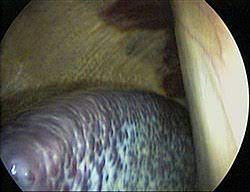

Say we have a rest endpoint to a collection, and we need to provide a way for users to specify filter criteria when querying this collection. Перевод слова spleen, американское и британское произношение, транскрипция, словосочетания, однокоренные слова, примеры использования. Listen to spleen | soundcloud is an audio platform that lets you listen to what you love and share the sounds you create. A cat on every drug and has every disease and slave to graystillplays. Learn about spleen location, spleen pain and other symptoms, and possible causes and treatments for enlarged spleen (splenomegaly). The spleen helps fight infection, keeps body fluids in balance, stores blood, and destroys old and damaged cells. A second batch of 56 samples (spleens and nodes), taken from 5 different areas was also. It is the largest organ in the body's lymphatic system, which is responsible for promoting. On ceus, the lesion is more. The spleen is a small organ, typically located on the left side of the body, behind the ribcage and stomach. Similar in structure to a large lymph node, it acts primarily as a blood filter. The spleen is rich in blood supplied via the splenic artery. Easily add dynamic filtering to your application.

On ceus, the lesion is more. Overview of the spleen anatomy, including location, microanatomy and function. Find out where your spleen is located. Webmd's spleen anatomy page provides a detailed picture, definition, and information about the spleen. | meaning, pronunciation, translations and examples.